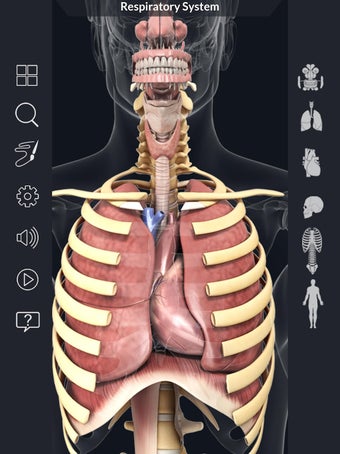

このアプリケーションは、高度にリアルな呼吸器系のモデルです。ユーザーは任意の角度および任意の平面から呼吸器系の解剖学を表示できます。ユーザーは360°回転し、ズームインおよびズームアウトして解剖学をよりよく研究することができます。ユーザーはまた、画面に描画するためのさまざまなツールを使用して写真を撮ることもできます。